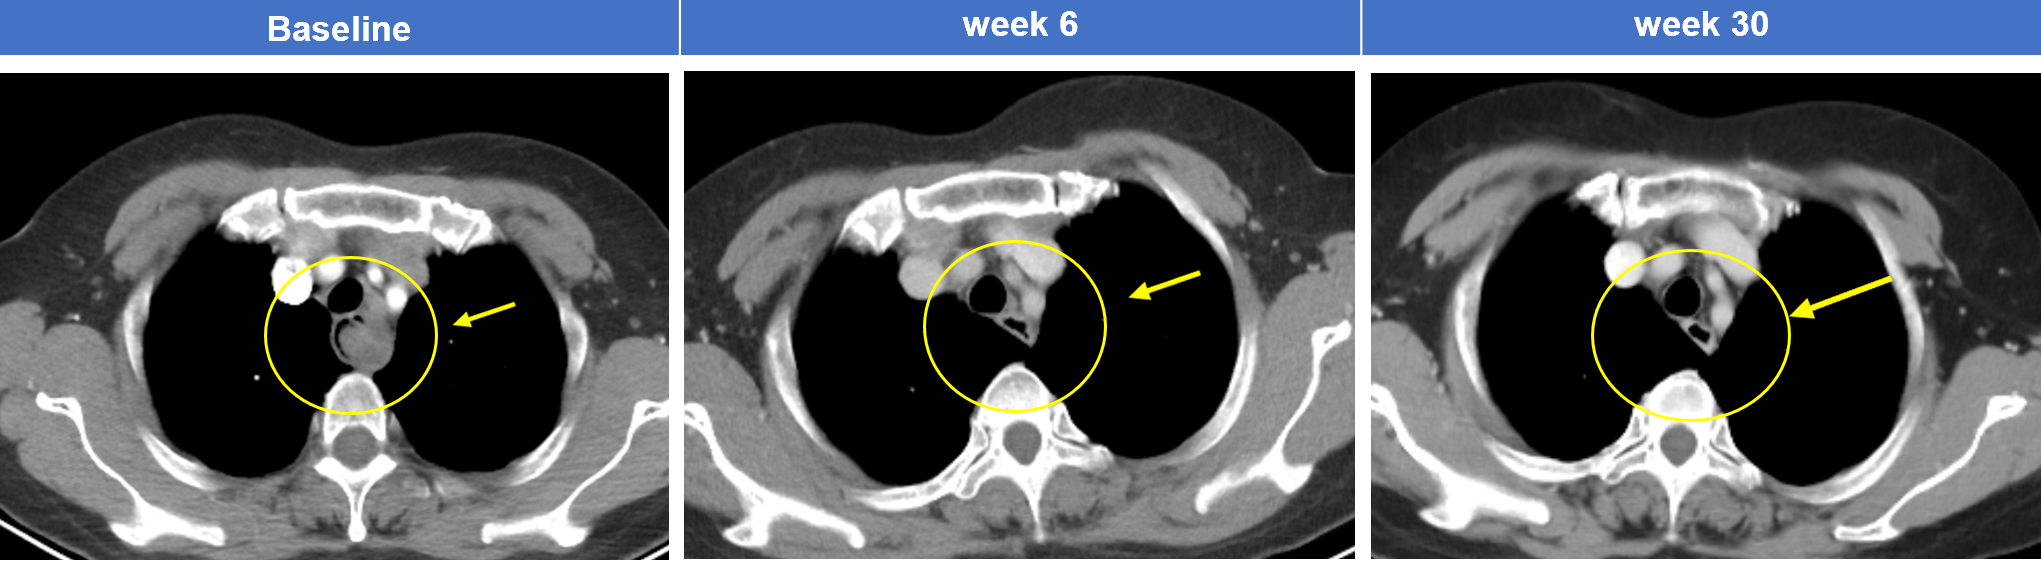

典型案例2